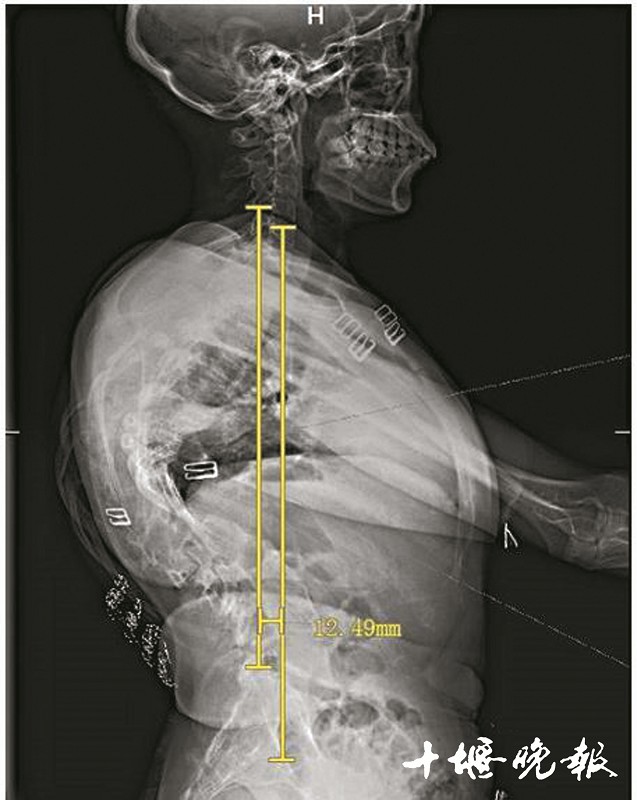

王欣手术前的X光片。

脊柱在胸后背拐了道90度的弯,并向后凸60度,后背隆起,身形扭曲,身高仅1.4米……过去30年,王欣(化名)始终无法面对这样“畸形”的自己,也没少遭人异样眼光。更可怕的是,由于脊柱严重侧弯,致使她的肺、胃等脏器受到挤压,呼吸和消化系统也受到影响。

经检查,王欣确诊为脊柱重度僵硬性侧后凸。其中,脊柱侧弯达90度,后凸达60度。从后背看,她的脊柱扭曲得像麻花。

很快,王欣被送进手术室。8小时后传来好消息:手术很成功,没有出现任何并发症。经术后评估,王欣90度的脊柱侧弯纠正了60度,60度的后凸纠正了30度,效果很好。“术中,王欣失血达3000毫升,得益于输血科的血液回收循环技术,保障了血液供应。”王达义说,王欣的骨骼质地坚硬,靠传统工具、老方法很难截断,而他们利用超声骨刀,这一问题便迎刃而解。

5个小时的手术很成功。两次手术,王欣先后共截除脊椎骨3节、肋骨4节。术后评估显示,王欣原本侧弯90度的脊柱,纠正了近80%,后凸畸形100%矫正。当她站立走路时,外观已和常人无异。术后,她的身高也由原来的1.4米增加到1.52米,比她丈夫还要高。